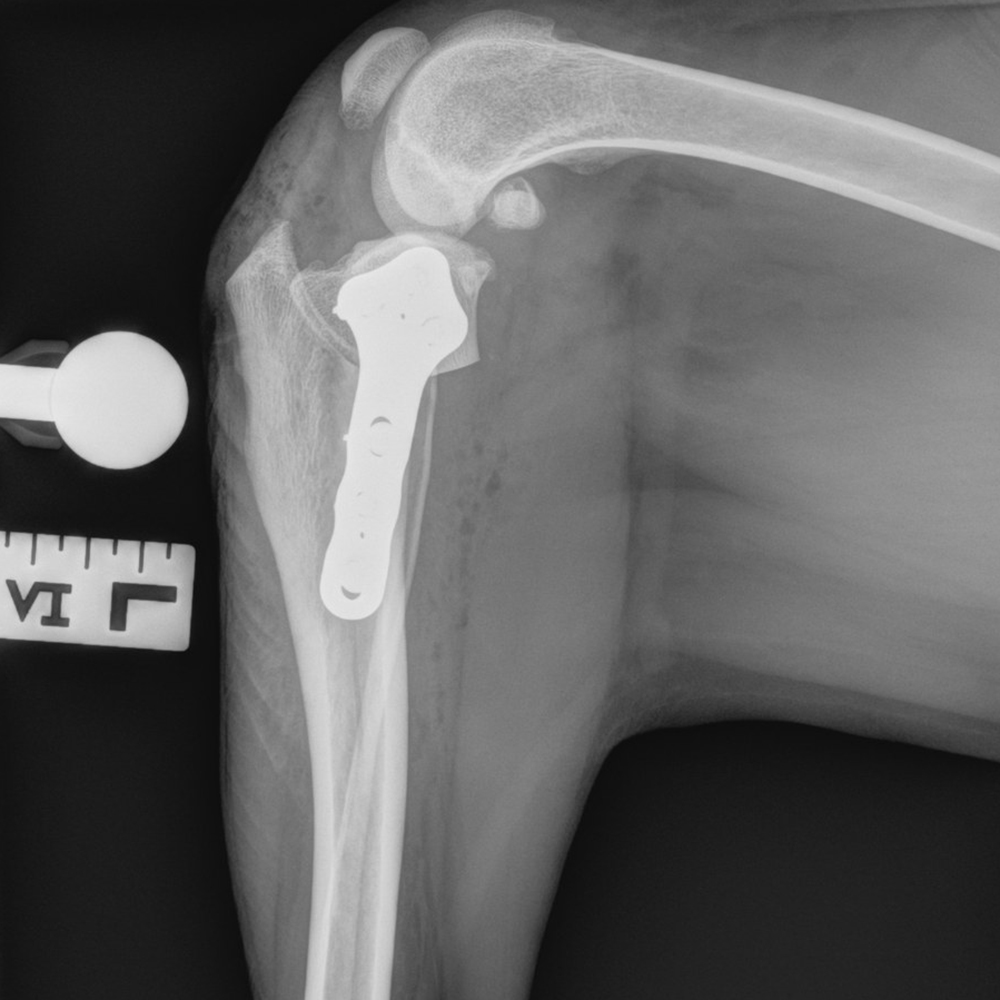

The RITA LEIBINGER Titanium TTA RAPID® Tiny, 2.0/2.4 TPLO and Titanium TPLO Swing, and our 2.0/2.4 Titanium CBLO implant systems and instrumentation are specifically designed for small patients, and can help overcome these challenges. They are typically smaller in size and have different geometries to accommodate the smaller bone structure of small dogs and cats.